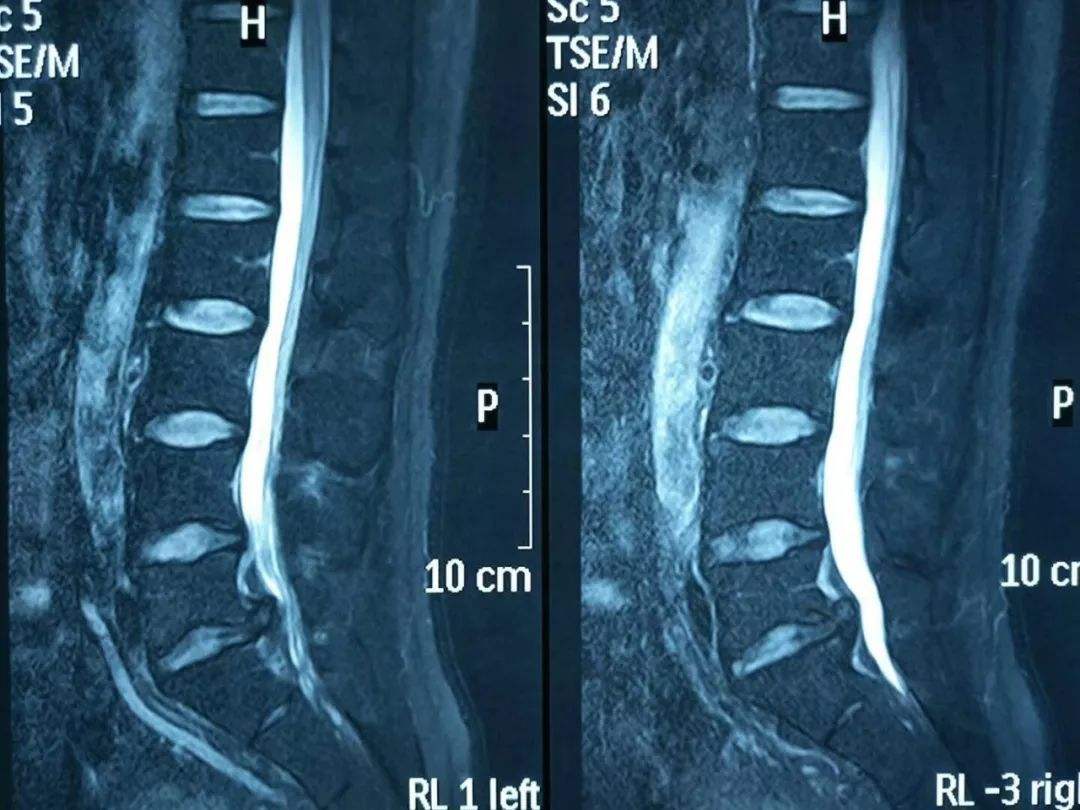

1. 治疗腰椎间盘突出

臭氧浓度:40μg/ml 腰椎盘内注射6~10ml;退针至盘外,椎管内注射10ml。

注射次数和间隔时间:一般注射1~2次,间隔3~5天